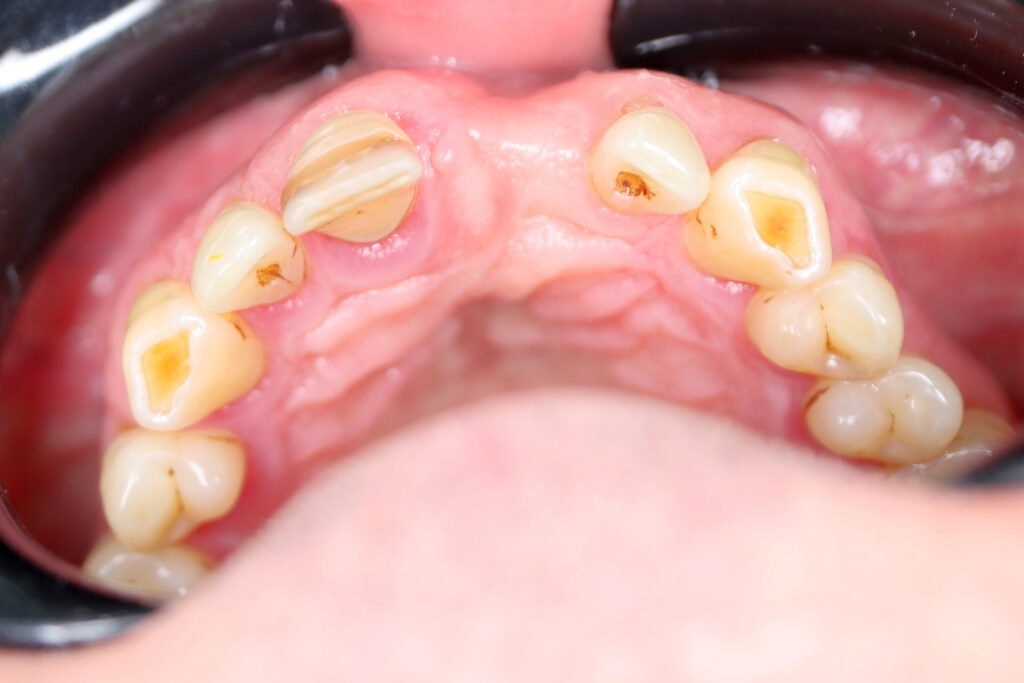

Результаты хирургического этапа